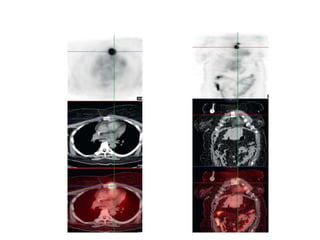

On the initial mammogram a marker is placed in the palpable tumor.

Due to the dense fibroglandular tissue the tumor is not well seen.

Ultrasound demonstrated a 37 mm mass with indistinct and angular margins and shadowing

On the initialmammogram a marker is placed in the palpable tumor. Due to the dense fibroglandular tissue the tumor is not well seen. Ultrasound demonstrated a 37 mm mass with indistinct and angular margins and shadowing